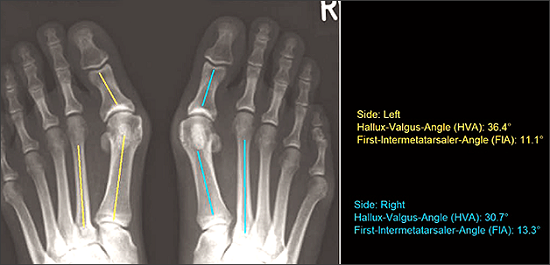

2. Xem xét tình trạng vẹo ngoài của ngón cái - Hallux Valgus

Hallux valgus là một cấu trúc bất thường ngón chân cái vẹo vào trong phía các ngón chân khác. Theo thời gian, cảm giác đau ở ngón chân từ từ tăng lên và khối u xương ở cạnh ngón chân hiện rõ. Nó ảnh hưởng lớn đến cuộc sống hàng ngày của chúng ta.

+ Phần mềm MediCAD đưa ra hình ảnh đa chiều, phân tích trước mổ thông qua tính toán tự động tất cả các góc độ có liên quan

+ Kết quả sau phẫu thuật có thể được mô phỏng dựa trên thông số bệnh nhân dễ dàng. Dữ liệu có sẵn của phần mềm cho phép các tùy chọn đo kích thước được cá thể hóa và nhiều implant có sẵn để lựa chọn.